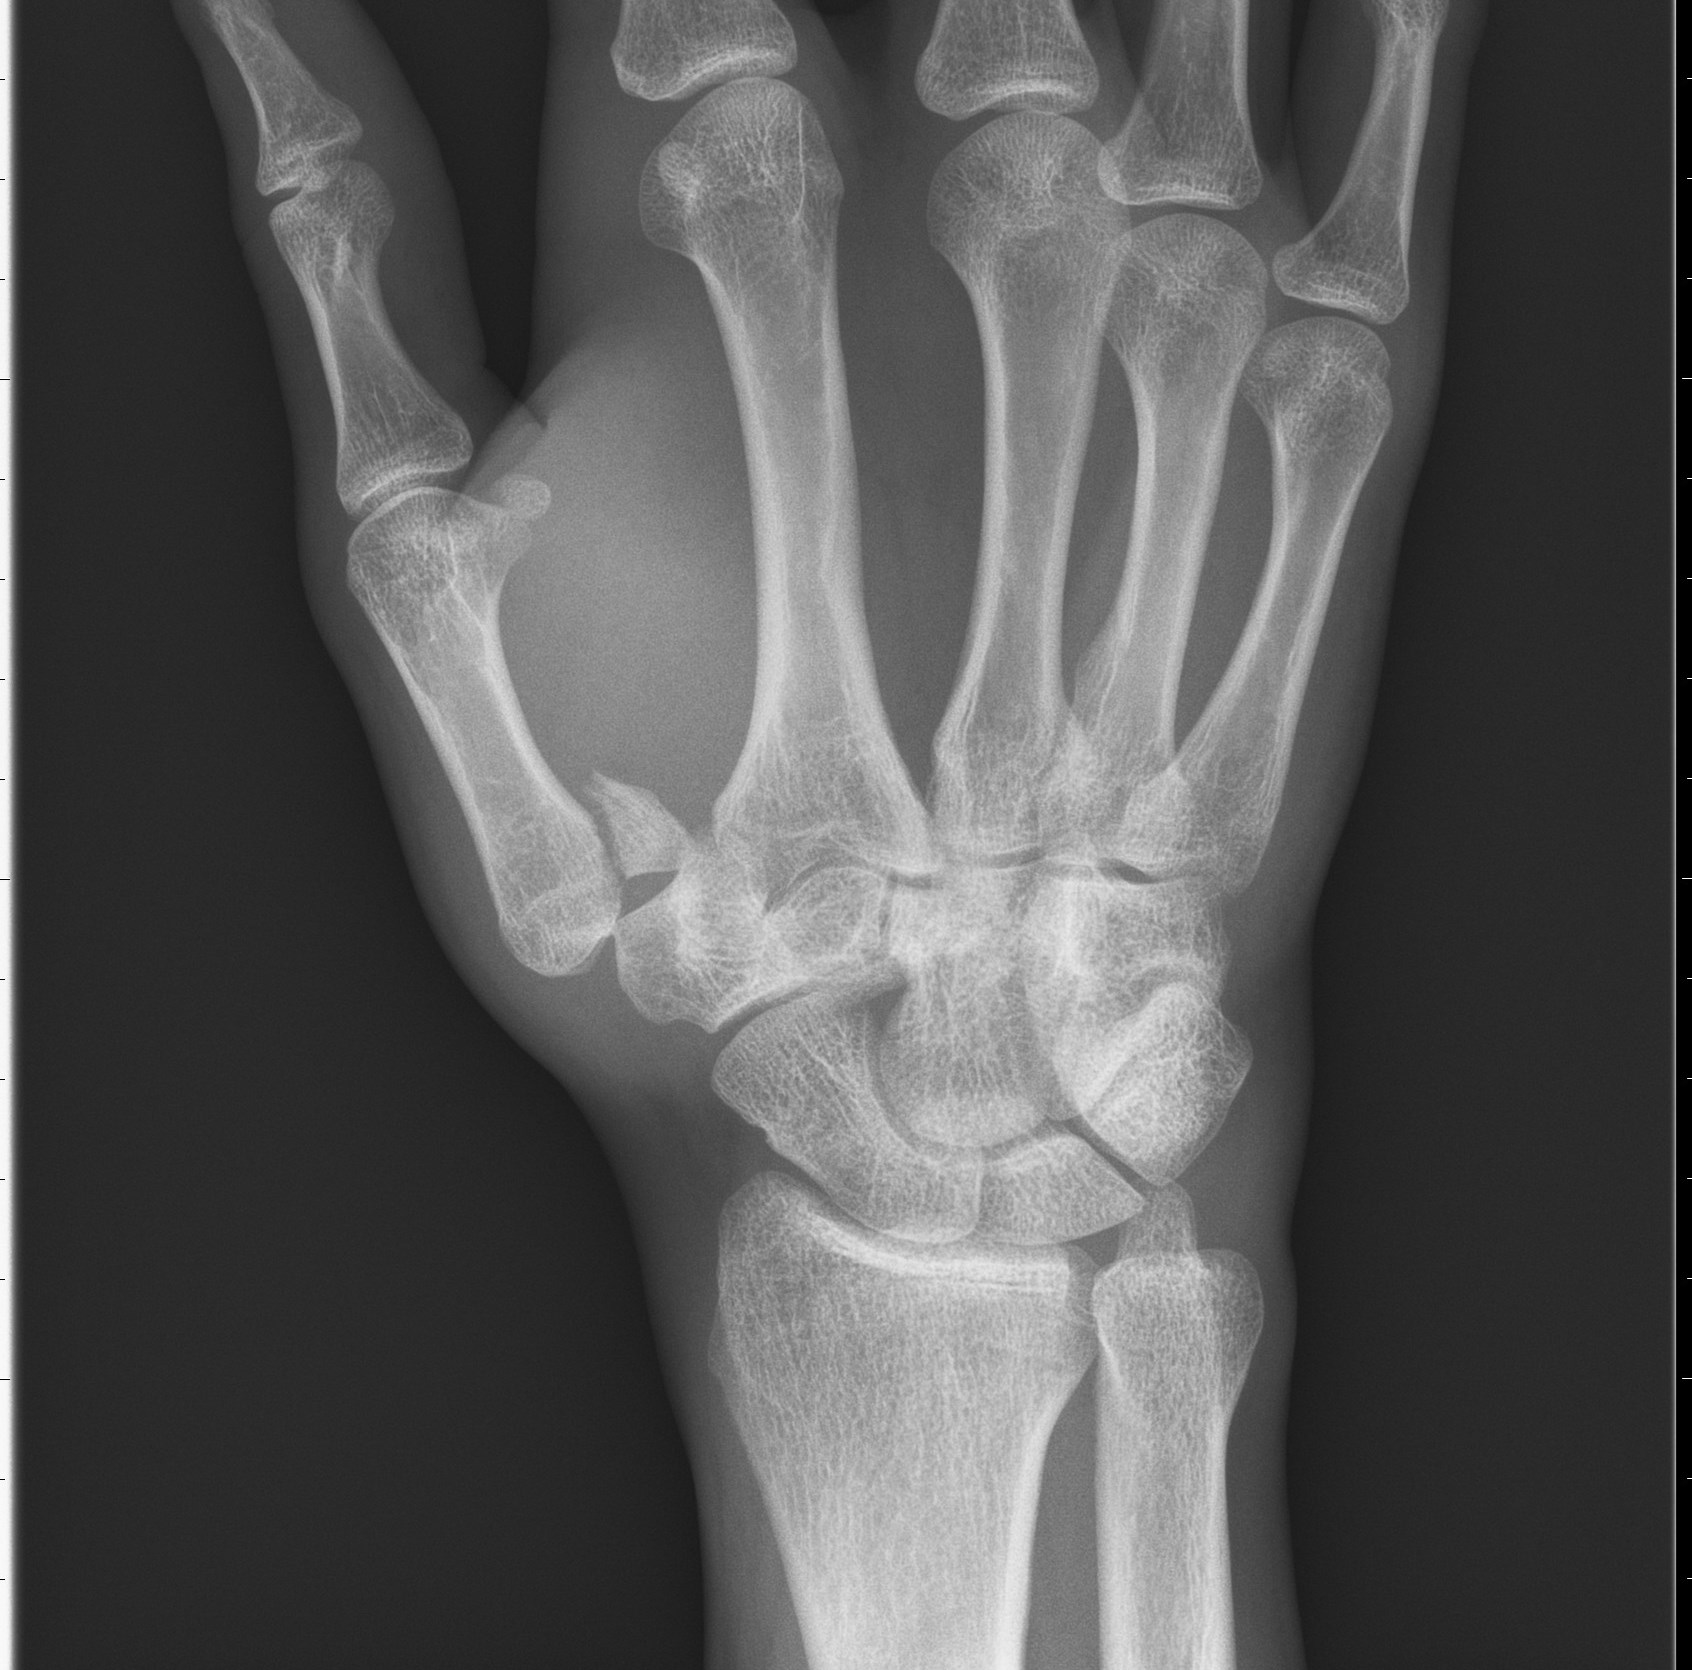

Scaphoideumfraktur

Symtom

Palpationsömhet i fossa Tabatiére, smärta vid axialt kompression av tummen samt vid dorsalextension respektive radialdeviation av handleden.

Drabbar ofta yngre individer i samband med sportutövning eller efter annat kraftigt dorsalextensionsvåld. Frakturen är ofta svår att identifiera på slätröntgen varför upprepade undersökningar och/eller CT/MR kan behövas.

Scaphoideum är dåligt vaskulariserad och ofta läker dessa frakturer (ffa proximala polfrakturer) långsamt; 3 månader i gips är normaltid! Gipsen skall immobilisera tumbas, handled och begränsa armens pro-supination. Utebliven läkning (pseudartros) är relativt vanligt och risken ökar om frakturen inte immobiliseras från skadetillfället.

Vid misstanke om scaphoideumfraktur (adekvat trauma, ömhet i fossa Tabatiére)

- Immobilisera i scaphoideumgips även om röntgen bedöms normal.

- Beställ då röntgenkontroll (utan gips) efter 10-14 dagar! Om röntgen är u a även efter 2 veckor, men status kvarstår: ordna snar MR- eller CT-undersökning!

Om skadan missas leder den mycket ofta till pseudartros och senare artros. En smärtsam pseudoartros kräver ofta att man tillför ben från crista illiaca vid operation och vid en handledsartros krävs någon typ av steloperation eller annat större ingrepp.

Det är tyvärr vanligt att frakturen missas då patienten kan uppleva symtomen som en distorsion, men det är också ganska vanligt att det missas av den undersökande doktorn. Detta sammantaget (s.k. 'patient's and doctors’ delay') innebär tyvärr att pseudoartrosoperationer är ganska vanliga.

Bennetfraktur

Bennetfraktur är en intraartikulär luxationsfraktur genom basen av metacarpale I. Metacarpalbasen tenderar att luxera genom APL senans dragning i radiell-proxmal riktning. Frakturen behöver därför i princip alltid reponeras och immobiliseras internt med stift. Kan se väldig beskedlig ut på primära bilder men dislocerar succesivt genom senans dragning – klassificeras därför som ”lurig”.

Mekanism vid Bennetfraktur

Bennetfraktur där det ulnara fragmentet i basen på metkarpalen hålls kvar med hjälp av ligament i karpus. På grund av drag i abductor pollicis longus (APL) uppstår nästan alltid en diastas i frakturen. Diastasen i ledytan ger sekundärt artros. Dessa frakturer kräver således exakt fixation – vanligen i form av stift eller skruv.